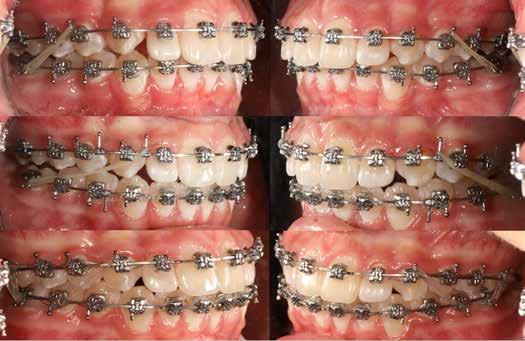

Dr. Ivana Dubovská, dr. Barbora Vágnerová, dr. Wanda Urbanová (Csehország), Dr. Veiszenbacher Éva, dr. Borbély Zoltán, dr. Borbély Péter (Dr. Borbély Fogszabályozási Stúdió, Budapest)

SZEMFOG ÉS KISŐRLŐ FORMÁZÁSA KISMETSZŐ APLÁZIA RÉSZÁRÁSSAL

TÖRTÉNŐ KEZELÉSE SORÁN

Absztrakt

A hiányzó oldalsó kismetszők részárással történő kezelése során a szemfogak és oldalsó fogak meziális mozgatása közben a fogszabályozó orvosnak csiszolással kell a fogak formáját igazítani. Már a kezelés elejétől a szemfog elcsiszolása nem csak az incizális részre kell hogy kiterjedjen, hanem az approximális, palatinális és a vesztibuláris felszín éli negyedére is. Így érhetünk el egy rövidebb klinikai koronát, a vesztibulo-orális méret csökkenését, egy incizális élet, valamint a szemfog megfelelő pozicionálását a kismetsző helyén. A túl széles szemfog megakadályozza a megfelelő interkuszpidáció kialakítását az oldalzónában. A palatinális felszín elcsiszolásával biztosítjuk az interferenciák nélküli metszővezetést, és a megfelelő overjetet a frontfogak enyhe érintkezésével. Ha a szemfogra a későbbiekben esztétikai pótlás készül, a megfelelő approximális elcsiszolás (az esztétikai fogorvossal történő egyeztetés után) biztosítja a zenith kívánatos pozícióját a későbbi felépítéshez. A mezializált kisőrlő palatinális csücskének elcsiszolására csak akkor van szükség, ha ez akadályozza a megfelelő fogérintkezést. Az első kisőrlő mindkét csücske fontos a már a szemfog helyén álló fog esztétikai és funkcionális beállításához.

Jelen beszámoló célja a fellelhető szakmai irodalom áttekintése, továbbá az eljárás klinikai lépéseinek bemutatása.

Kulcsszavak: szemfog mezializáció, szemfogformázás, szemfog elcsiszolás, első kisőrlőformázás, első kisőrlő elcsiszolás, hiányzó oldalsó kismetsző (aplázia)

A szemfog oldalsó kismetsző helyére történő bemozgatása során a fog átalakítása javasolt a két fog eltérő morfológiai adottságai miatt (1. a-b. ábra). A fog kontúrozása, vagy úgynevezett formázása magába foglalja az approximális felszínek elcsiszolását, valamint a többi fogfelszín igazítását a kívánt fogformának megfelelően [1].

A kismetsző és szemfog klinikai koronái közötti eltérések a következőek: mezio-disztálisan keskenyebb oldalsó metsző, csücsök hiánya, egyenes éli lefutás, és a vesztibuláris felszín domborulata is kevésbé kifejezett [2,3]. A szemfoggal összehasonlítva, az oldalsó metsző rendszerint rövidebb és keskenyebb mind mezio-disztálisan, mind vesztibulo-orálisan. Az átformázott szemfog és az oldalsó metsző anatómiai alakja közötti egyezés függ az elülső zóna mint egység formájától is. Kataoke és Nishimura három alapformát határozott meg az elülső fogak tekintetében: négyszögletes, óvóid és háromszög formájú [4]. A frontfogak vesztibuláris felszínét a három kúp egységeként írják le (kúpos fejlődési mamelonok): meziális, disztális és centrális. A szemfogak esetén a három közül a központi a legdominánsabb, de nem ugyanez a helyzet az oldalsó metsző esetében. Háromszög alakú fogkorona esetén a meziális és disztális érvényesül jobban, négyszögletes formánál mindhárom egyenlő arányban domborodik, míg óvóid forma esetén a középső kerül túlsúlyba. Ennek megfelelően a szemfog csücskét el kell csiszolni, és kompozit felépítéssel az elülső anatómiai formához illő oldalsó metsző alakzatot kialakítani a szélső élek megfelelő hangsúlyozásával [5]. Amennyiben az elülső fogak formája háromszögletes, akkor kifejezett meziális és disztális felépítésekre lesz szükség. Négyszögletes forma esetén a szemfog meglévő centrális kúposságát kiegyensúlyozva építik fel a fogat. Az elülső fogak ovoid alakzata esetén a meziális és disztális kúposságot alig vagy egyáltalán nem hangsúlyozzák

A szemfog elcsiszolásához piros gyémántfúró javasolt, finom szemcsézettséggel, 27-76 µm (okkluzálisan lekerekített – Rodentica, speciális hegyű 806314466514031, Komet 8833), gyorsítóval (max 160 000 fordulat/perc) megfelelő hűtés mellett, legalább 50 ml/perc. Ezt követi a felület kidolgozása és polírozása sárga gyémántcsiszolóval, extra finom szemcsézettséggel, 10-36 µm (Rodentica 806314466504031) és narancssárga Sof-Lex korongokkal (finom alumínium-oxid szemcsék 3-40 µm, extra finom, narancssárga-sárga, alumínium-oxid kristályok mérete 1,7 µm) könyökdarabban (25000 fordulat/perc) megfelelő hűtés mellett min. 50 ml/perc (2. a-d. ábra).

A szemfog megfelelő inklinációjának eléréséhez az oldalsó metsző helyén a palatinális felszínt is el kell csiszolni. Ennek a felületnek nem szabad interferenciát okoznia a harapásban, és lehetővé kell tennie a megfelelő metszőfog-vezetést [14]. A formázás előtt meg kell vizsgálni a szemfog vesztibulo-orális pozícióját. Lapos vesztibuláris felszínnel rendelkező szemfog esetén szükség lehet egy elsőrendű hajlításra a középső metsző és szemfog között (főleg, ha a szemfogon egy oldalsó metsző bracket van, melyben a beépített in-out érték magasabb) annak érdekében, hogy elérjük a megfelelő vesztibulo-orális pozíciót a fognyak szintjén, és elkerüljük a palatinális elcsiszolást (3. a-b ábra), [39].

Abban az esetben, ha a szemfognak kifejezettebb a központi lóbusa, a palatinális felszínről is el kell csiszolni, nem csak a vesztibuláris felszínről [40, 41]. A vesztibuláris felszín kifejezett elcsiszolása esetén ez már a dentint is érintheti, ami megnehezíti az esztétikai helyreállítást (a sárga dentin átüthet és a ragasztás is nehezebb ehhez a felülethez). Ezért a vesztibulárisan domború szemfogakat javasolt palatinálisabban pozicionálni, ami – együtt

38 e-Journal ORTHODONTIA

2. a–d ábrák

a nagyobb mértékű palatinális elcsiszolással – lehetővé teszi a felépítmény kiterjesztését a vesztibuláris felszínen és a központi lóbus álcázását [39].

A zománc elcsiszolásának mértékét az orális és incizális felszínen a harapás határozza meg, ennek vizsgálatához tükröt és artikulációs papírt használunk [36]. Ideálisan, teljes interkuszpidációban a frontális kontakt olyan enyhe, hogy az artikulációs papír kicsúszik, míg propulzióban, metsző fogvezetésnél a jelölésnek a palatinális felszín incizális harmadában kell lennie mind a középső metszőn, mind a szemfogon. A gyémánteszközök legalkalmasabb formája a palatinális elcsiszoláshoz a lándzsa és rögbi alakú (Komet 0640, piros finom lándzsa Rodentica 806314257514020 (max. 300 000 fordulat/perc), rögbi Rodentica 800314278514020 finom piros (27-76 µm) gyorsítóban. Ezt követően könyökdarabba fogott Sof-Lex korongokkal szükséges polírozni (4. a-b. ábra).

Szemfog mezializációt követően történik az approximális felszínek igazítása. Elérjük a megfelelő mezio-disztális szélességet, és a kontaktpont incizális irányba helyeződik át. Ebben a fázisban mindig szükséges egyeztetni az esztétikai pótlást készítő fogorvossal a szükséges szemfogformáról és a későbbi felépítmény pontos helyzetéről. Az esztétikai fogorvosnak kell eldöntenie a meziális és disztális felszínek elcsiszolásának mértékét is.

Az ideális mezio-disztális fogméretet arányok alapján határozzuk meg. Az oldalsó felszínek elcsiszolására alkalmazott

eszközöknek egyeneseknek kell lenniük (az elején), melyek alkalmasak a szemfog domborulatainak elcsiszolására és az approximális felszínek párhuzamosítására a fog tengelyével [38]. A legalkalmasabbak a keskeny, rövid, tűhegy alakú fúrók (speciális, rövid, piros tűhegyű Rodentica 806314465514016 (Komet 1385), sárga Rodentica 806314465504016), hosszú tűgyémánt (Komet 0574 és finom piros lándzsa alakú gyémánt Rodentica 806314249514009, extra finom sárga lándzsa alakú gyémánt Rodentica 806314249504009) és hegyes lándzsa (Rodentica sárga hegyes lándzsa 806314540504010, piros 806314540514010) max. 450 000 fordulat/perc (5. a-e. ábra). Zachrisson szerint az approximális felszíneket gyémántfúrókkal és háromszög alakú tűkkel (okkluzális kontúrozók) alakítjuk és kerekítjük le (Rodentica 466, Komet 8833), [42, 35], (6. a-b ábra). Így a pontszerű kontakt területek kiszélesednek. Ezt követi a bukkális és palatinális felszínek megfelelő anatómiai formájának kialakítása. A lekerekítetlen élek megnehezítik a megfelelő pótlás elkészítését, valamint megnövelik a szuvasodás és parodontális érintettség veszélyét [33].

A javasolt eszközhasználati sorrend a következő: piros gyémántfúró (finom 27-76 µm), sárga gyémántcsiszoló (extra finom, 10-36 µm) gyorsítóban megfelelő hűtéssel (5,6 ábra.). Alkalmazhatunk gyémántkorongokat vagy oszcilláló mozgásokat végző korongokat is. A polírozást Sof-Lex korongokkal vitelezzük ki (finom-narancssárga 3-40 µm, extra finom – narancssárga-sárga, 1-7 µm), [43,33], (7. a-b ábra). Az approximális felszínek elcsiszolása több lépésben történik megfelelő vízhűtés alkalmazásával és helyi fluoridálással.

3. a–b ábra: .019x.025” acél mint befejező fogszabályozóív vesztibuláris hajlításokkal a 11-13., a 21-23., valamint a 24-25. és a 14-15. fogak között. 4. a-b. ábra: A szemfog palatinális felületének formázása (a, Rodentica 257) és polírozása narancssárga Sof-Lex koronggal (b). A braketeket már eltávolították ezekről a fogakról.

Kisőrlő becsiszolása

Ha a szemfog helyére mezializált kisőrlő intrúziójára nincs is szükség, a palatinális csücsök akkor is akadályozhatja a harapást és a szemfogvezetést [44]. Ezekben az esetekben elcsiszoljuk a palatinális csücsköt (8. a-b ábra) piros gyémántcsiszolóval (finom, 27-76 µm, éli formázóval – Rodentica speciális tűhegy 806314466514031, Komet 8833 vagy GD – lándzsa Rodentica 806314257514020, Komet 0640) gyorsítóban (max 160 000 fordulat/perc) vízhűtés mellett, min. 50 ml/perc [39]. Extra finom sárga gyémántcsiszolóval polírozunk, 10-36 µm szemcsézettséggel (sárga éli csiszoló Rodentica speciális tűhegyű 806314466504031, GD – sárga lándzsa alakú Rodentica 806314257504020) és narancs Sof-Lex korongokkal (3M finom, narancssárga-alumínium-oxid kristály 3-40 µm nagysággal, extra finom, narancssárga-sárga, 1-7 µm alumínium-oxid kristályokkal) könyökdarabban (25 000 fordulat/perc) legalább 50 ml/ min. hűtéssel. Az elcsiszolást több lépésben végezzük, és ezt helyi fluoridalkalmazás követheti.